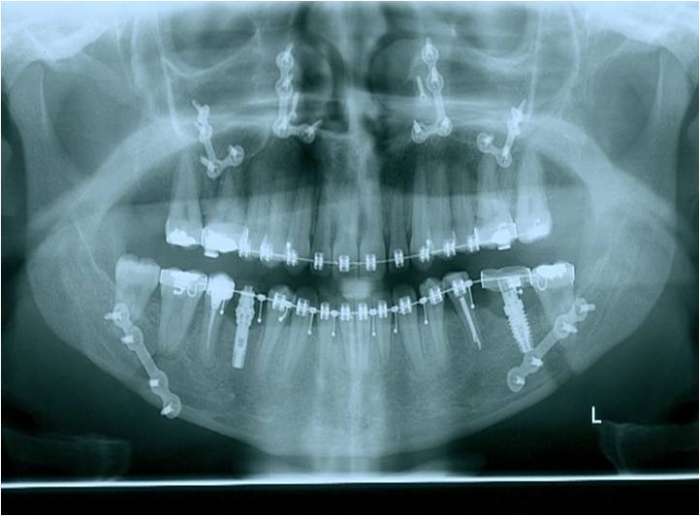

Raio x panorâmico inicial

Raio x panorâmico após a cirurgia